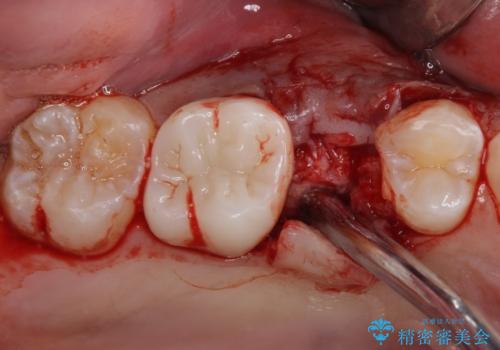

破折して抜歯が必要となった歯の後ろの歯は、根管治療が必要な状態であったので、根管治療を行い、矯正治療後にインプラント部の補綴治療と同時にセラミッククラウンを装着しました。